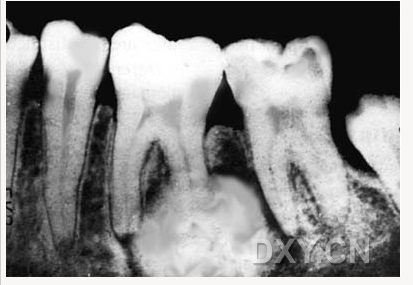

根尖囊腫